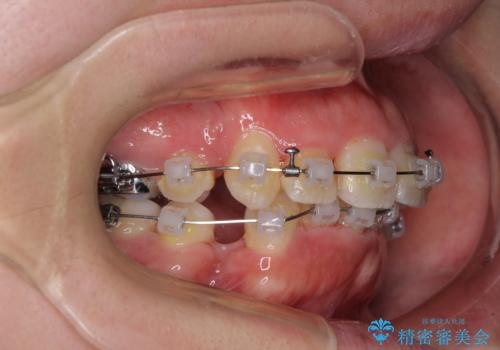

- 矯正装置

- クリアブラケット

- 上下の八重歯やデコボコを気にして来院された患者様です。

上下ともに八重歯が顕著であったので、上下左右第一小臼歯4本を抜歯し、補助装置を使用して速やかに改善しながら、ワイヤー装置にて矯正治療を行うこととしました。

気になっていた八重歯は装置装着から3か月ほどで解消されました。

2年以内を目標として治療を開始しましたが、1年半ほどで終えることができました。